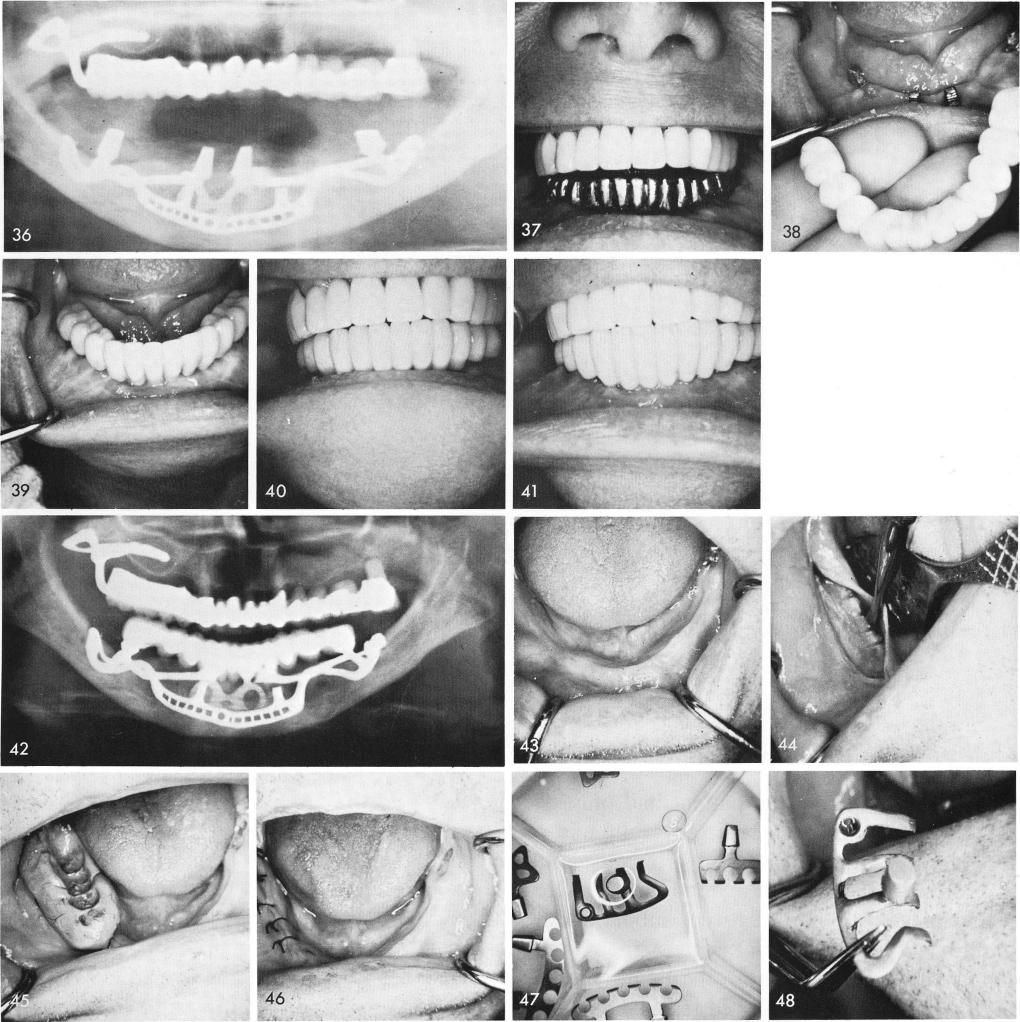

the subperiosteal implant and anterior blade, fig. 36. Castings are fitted, fig. 37, and the completed prosthesis is cemented with hard cement, figs. 38, 39, and the overjet and overbite were still greatly reduced, figs. 40, 41. The post-operative x-ray, fig. 42.

In a totally edentulous situation, fig. 43, it is most important to first prepare the lingual side of the mylohyoid ridge with several shallow grooves and take an impression and bite (Input) for a unilateral subperiosteal implant, figs. 44, 45. The tissues are then closed, fig. 46. At the next visit the sterilized implants, fig. 47, are ready to be fitted and inserted. The unilateral subperiosteal implant must first be tried in, fig. 48, because a full arch temporary splint is much better

1 X ray of mandibular subperiosteal implant and anterior blade implant